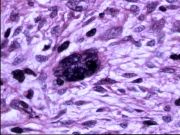

| 2021年12月10日 (五) 13:15 | 14号切片-纤维肉瘤-镜下观2.jpg (文件) |  |

143 KB | Cirno.9 | 基于MsUpload的文件上传 | 1 |